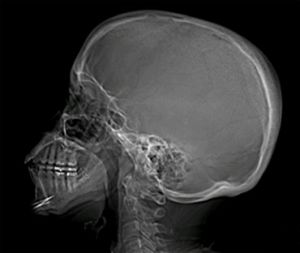

Подтверждение диагноза

Диагноз устанавливается с помощью метода, который может подтвердить наличие предполагаемой патологии и предоставить полное представление о состоянии вен головного мозга, особенно яремных вен.

Наиболее часто используется магнитно-резонансная томография (МРТ).

Среди других полезных методов диагностики можно выделить:

- рентгенографию черепа;

- флебографию;

- обследование глазного дна.